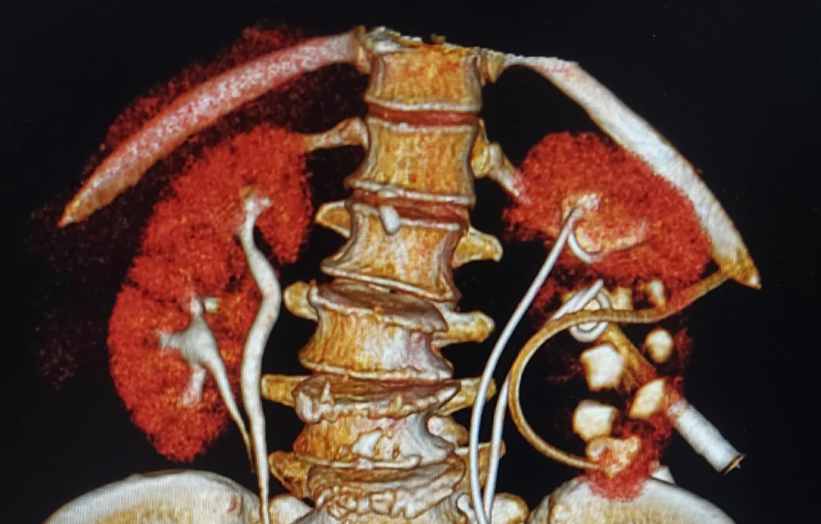

Hình ảnh trên phim chụp của người bệnh

Qua chẩn đoán hình ảnh, các bác sĩ phát hiện bệnh nhân bị sỏi niệu quản gây ứ nước ở đơn vị thận dưới bên trái, trong cấu trúc thận đôi hoàn toàn ở cả hai bên. Tình trạng này trở nên phức tạp hơn do hẹp niệu quản từ ca mổ cũ, khiến phẫu thuật gặp nhiều thách thức.